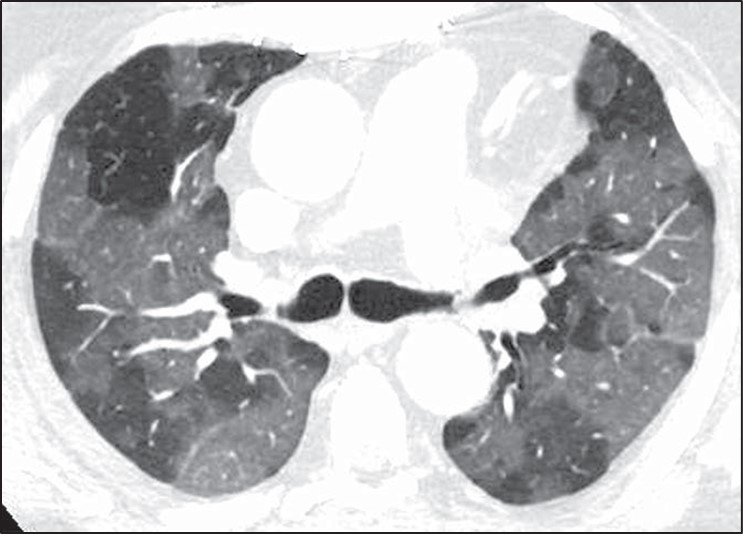

None of these features are perfect in making this distinction, however. For instance, diseases characterized by ground-glass opacity may occasionally be geographic with sharp borders (Fig. 9).

Fig. 9—Axial high-resolution CT scan shows ground-glass opacity due to SARS-CoV-2 infection. Sharp borders between areas of opaque and lucent lung usually suggest that lucent lung is abnormal and pattern is mosaic perfusion. However, sharp borders may occasionally be seen in ground-glass opacity, such as in this case. Normal lung and areas of ground-glass opacity show marked difference in attenuation.

In these cases, the absolute difference in attenuation between the two regions of lung may be helpful. Mosaic perfusion typically results in a relatively subtle difference in attenuation between the diseased lucent lung and the normal opaque lung. Ground-glass opacity, on the other hand, typically shows a more marked difference in density between the two areas [21]. That being said, when mosaic perfusion results in significant shunting of blood away from the diseased areas, a greater difference in lung attenuation may be present. These cases are not infrequently misinterpreted as ground-glass opacity. Another challenge in the distinction between mosaic perfusion and ground-glass opacity is that many cases of mosaic perfusion will not show a significant difference in vessel size between the lucent and opaque lung. Last, pulmonary vascular diseases characterized by mosaic perfusion will not show air trapping on expiratory CT. Thus, expiratory CT is not helpful in the diagnosis of diseases such as chronic pulmonary embolism [22].